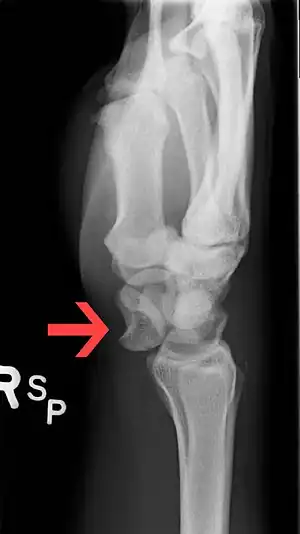

Dislocated lunate

The lunate bone is the most frequently dislocated carpal bone.